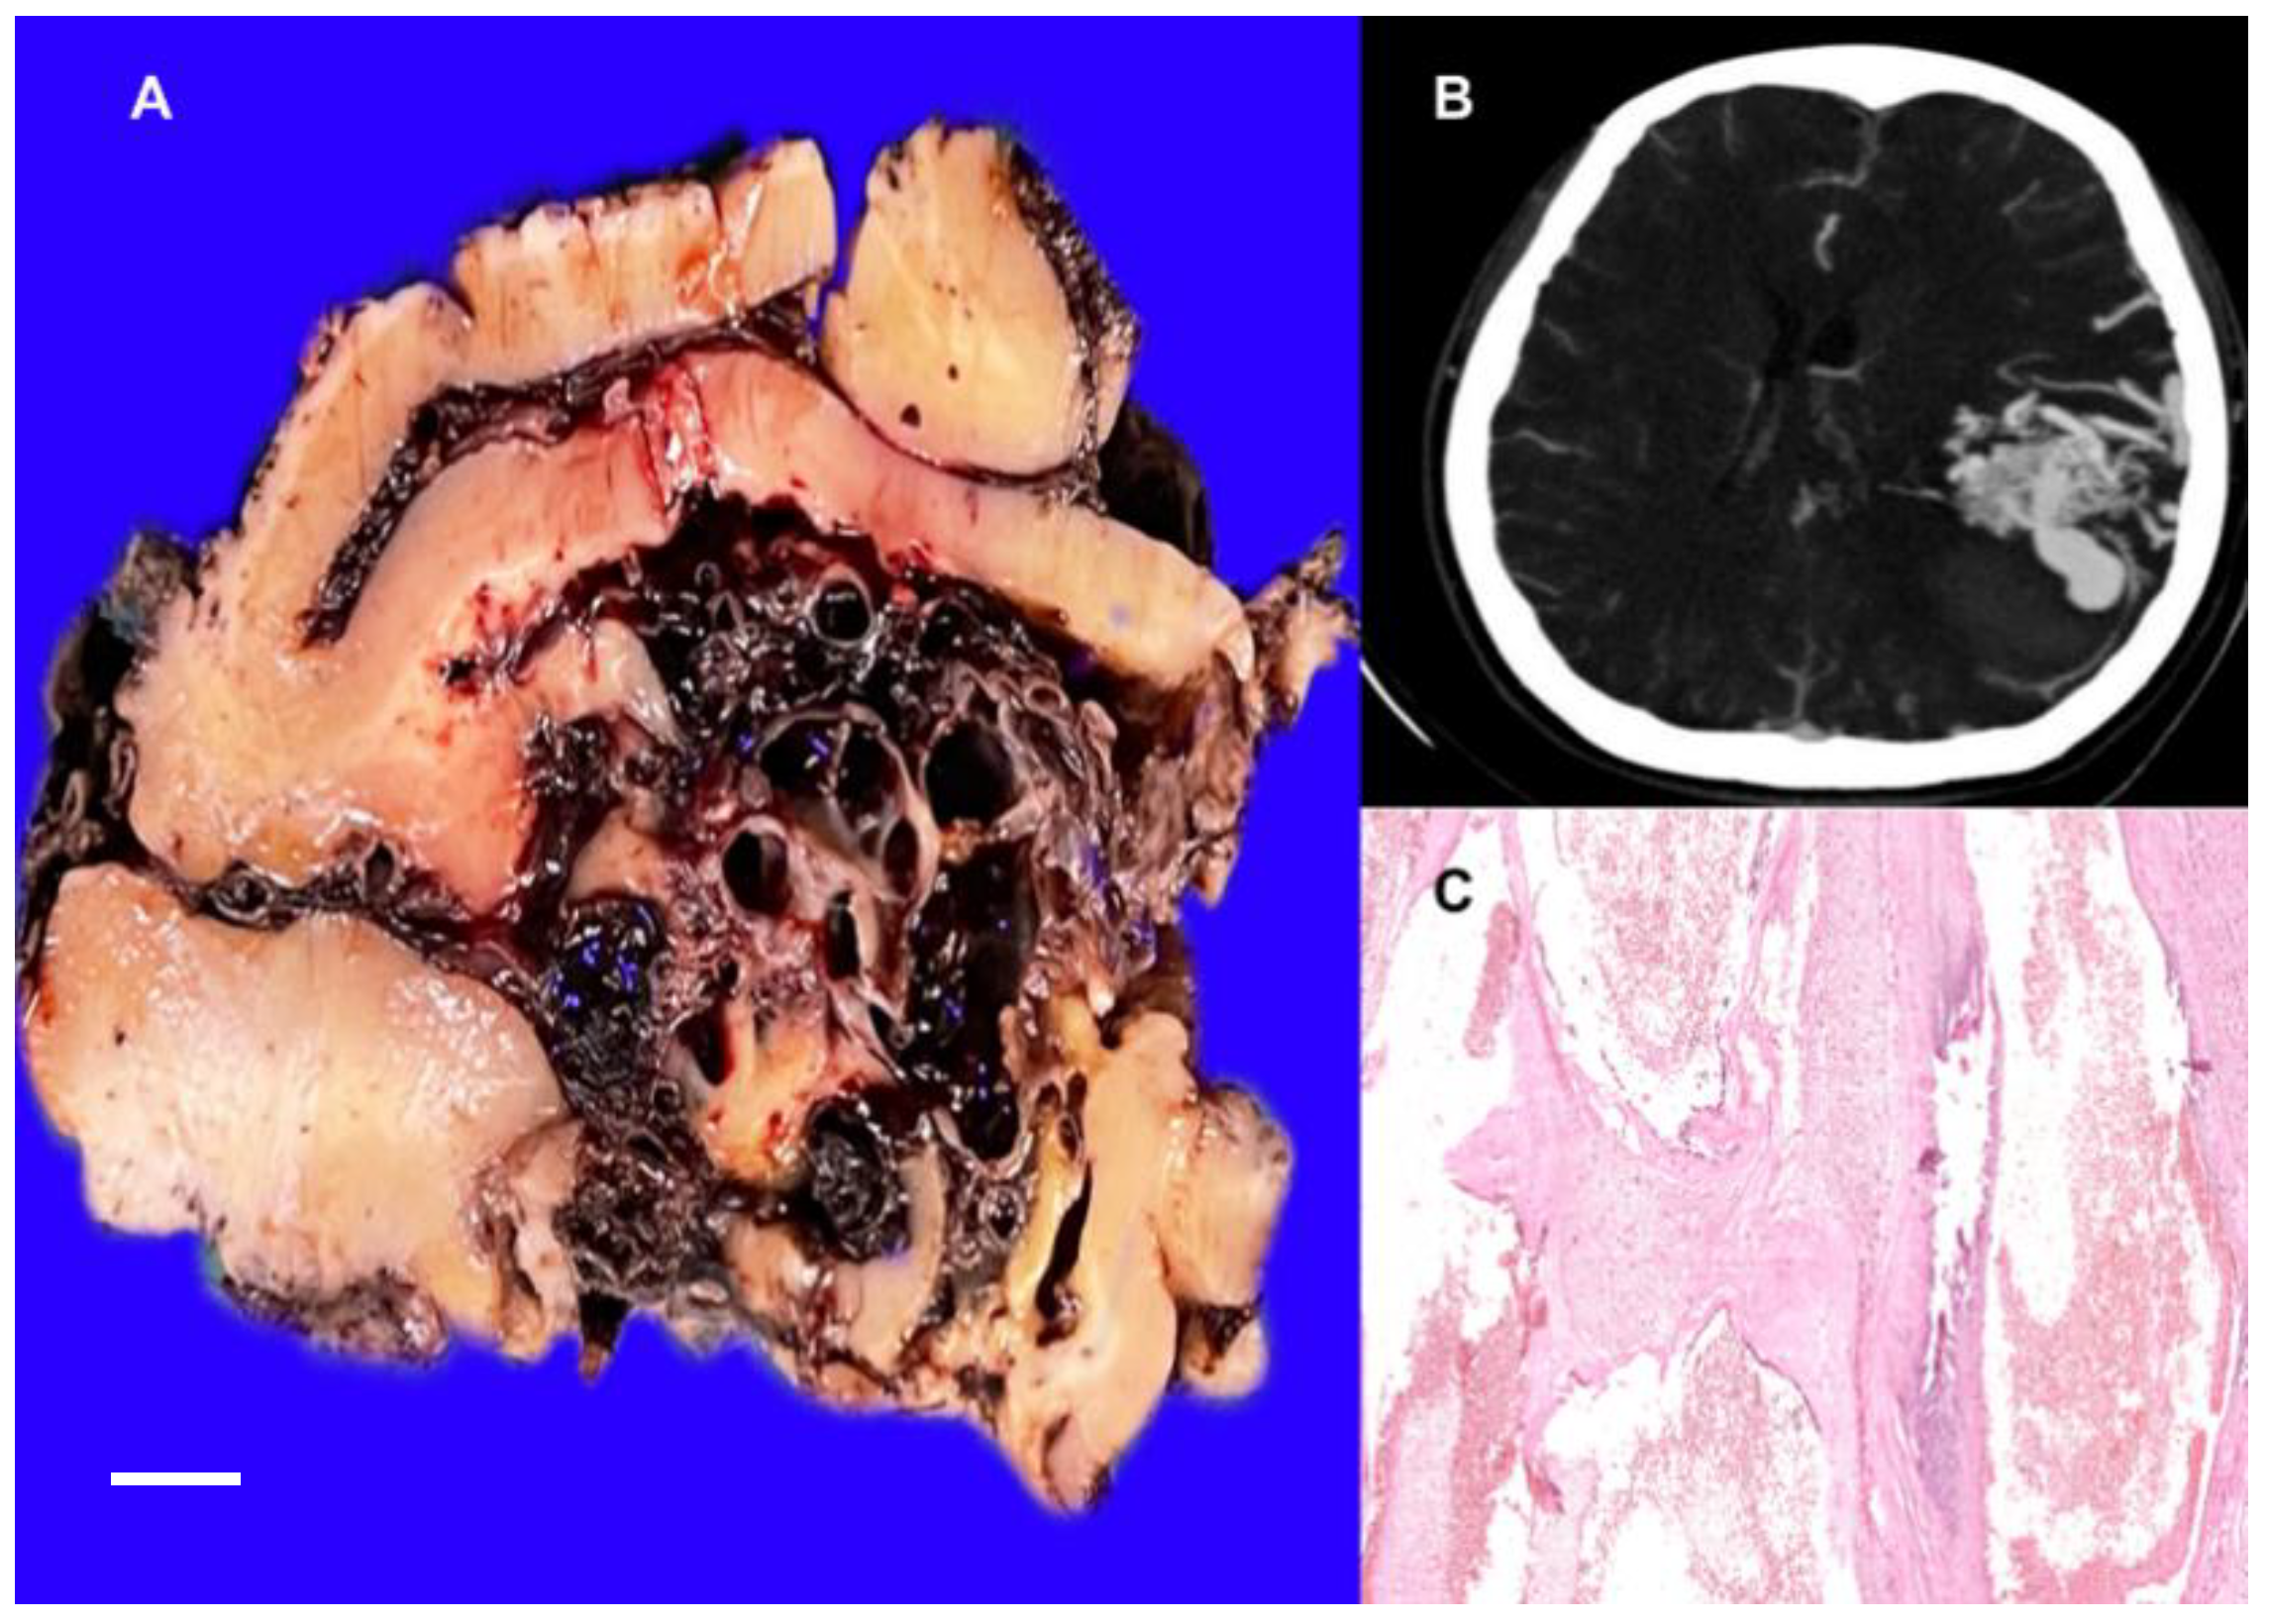

3.1.2. Brain Cavernous Angiomas

3.2. Arteriovenous Malformation (AV Angioma, Cirsoid Angioma)

- Liu, Y.; Liang, Y.; Tong, F.; Huang, W.; Tinzing, L.; Le Grange, J.M.; Wang, F.; Zhou, Y. Sudden Death from an Epileptic Seizure Due to Capillary Telangiectasias in the Hippocampus. Forensic. Sci. Med. Pathol. 2019, 15, 243–248. [Google Scholar] [CrossRef]